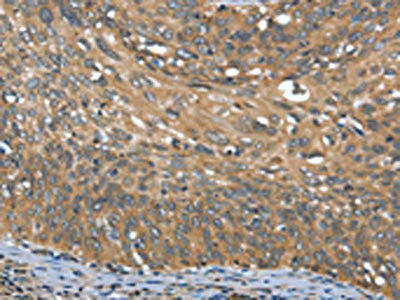

The image on the left is immunohistochemistry of paraffin-embedded Human cervical cancer tissue using CSB-PA928803(OPRD1 Antibody) at dilution 1/20, on the right is treated with synthetic peptide. (Original magnification: ×200)

The image on the left is immunohistochemistry of paraffin-embedded Human liver cancer tissue using CSB-PA928803(OPRD1 Antibody) at dilution 1/20, on the right is treated with synthetic peptide. (Original magnification: ×200)